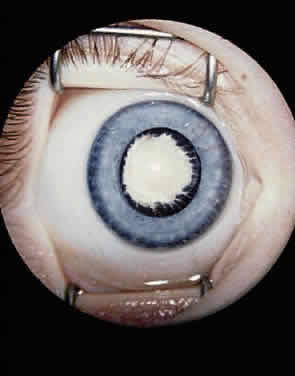

CLINICAL FEATURES